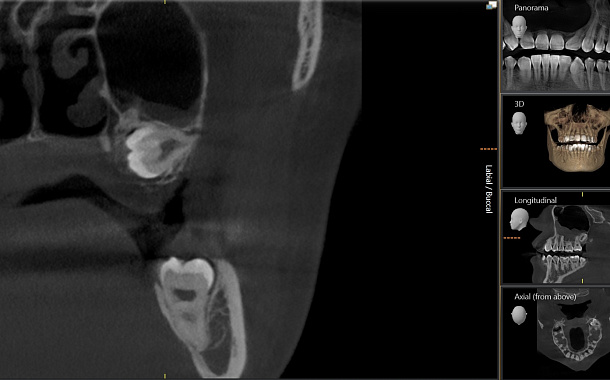

• компьютерную томографию. Обследование в формате 3D на томографе дает полную картину состояния зубочелюстной системы, что очень важно для грамотного планирования удаления.

Сложное анатомическое расположение и анатомия самих зубов, близкое расположение важных анатомических образований (нижнечелюстной канал, гайморова пазуха) и их взаимосвязанное расположение с корнями «восьмых» зубов, требует от врача-хирурга тщательного анализа клинической ситуации, данных 3D рентгенографии и оценки всех возможных рисков и осложнений, как во время операции, так и после ее проведения.

Компьютерная томография челюстно-лицевой области: 3D сканирование, аксиальная проекция, серия профильных изображений (сагиттальные срезы), панорамная рентгенография.